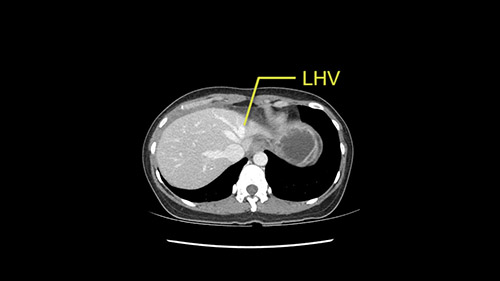

Anatomically, to plan for a left lateral segmentectomy, it’s relatively easy as far as liver surgery goes. I know that I'm going to be looking for the left hepatic vein which will be divided at some point either towards the end at the back near the vena cava or through the middle of the left lateral segment.

The transection line will be a little more obvious. There’s a little patch of focal fat here in Segment 4b but we’ll describe the transection line probably through the mid portion of Segments 4a and b up to the top. Up at the top, the left hepatic vein can be taken. There’s a Segment 3 vein or the so-called falciform vein it’ll be rudimentary so I think we’ll be able to get around the left hepatic vein and leave the middle [hepatic] vein intact because it’s free of tumor.

The other option of course is to do an anatomical left hepatectomy. In that case, I will start mobilizing of course the left lobe and try to find the ligamentum venosum, take it down and go around the left hepatic vein. I think, importantly in these cases and in this case, as you can see in the venous phase, that’s clearly a moment to stop. Because the left hepatic vein is pretty close to the middle hepatic vein as sometimes it is so you may need to dissect a little bit the parenchyma on top of the left hepatic vein to be able to go around the left hepatic vein safely.